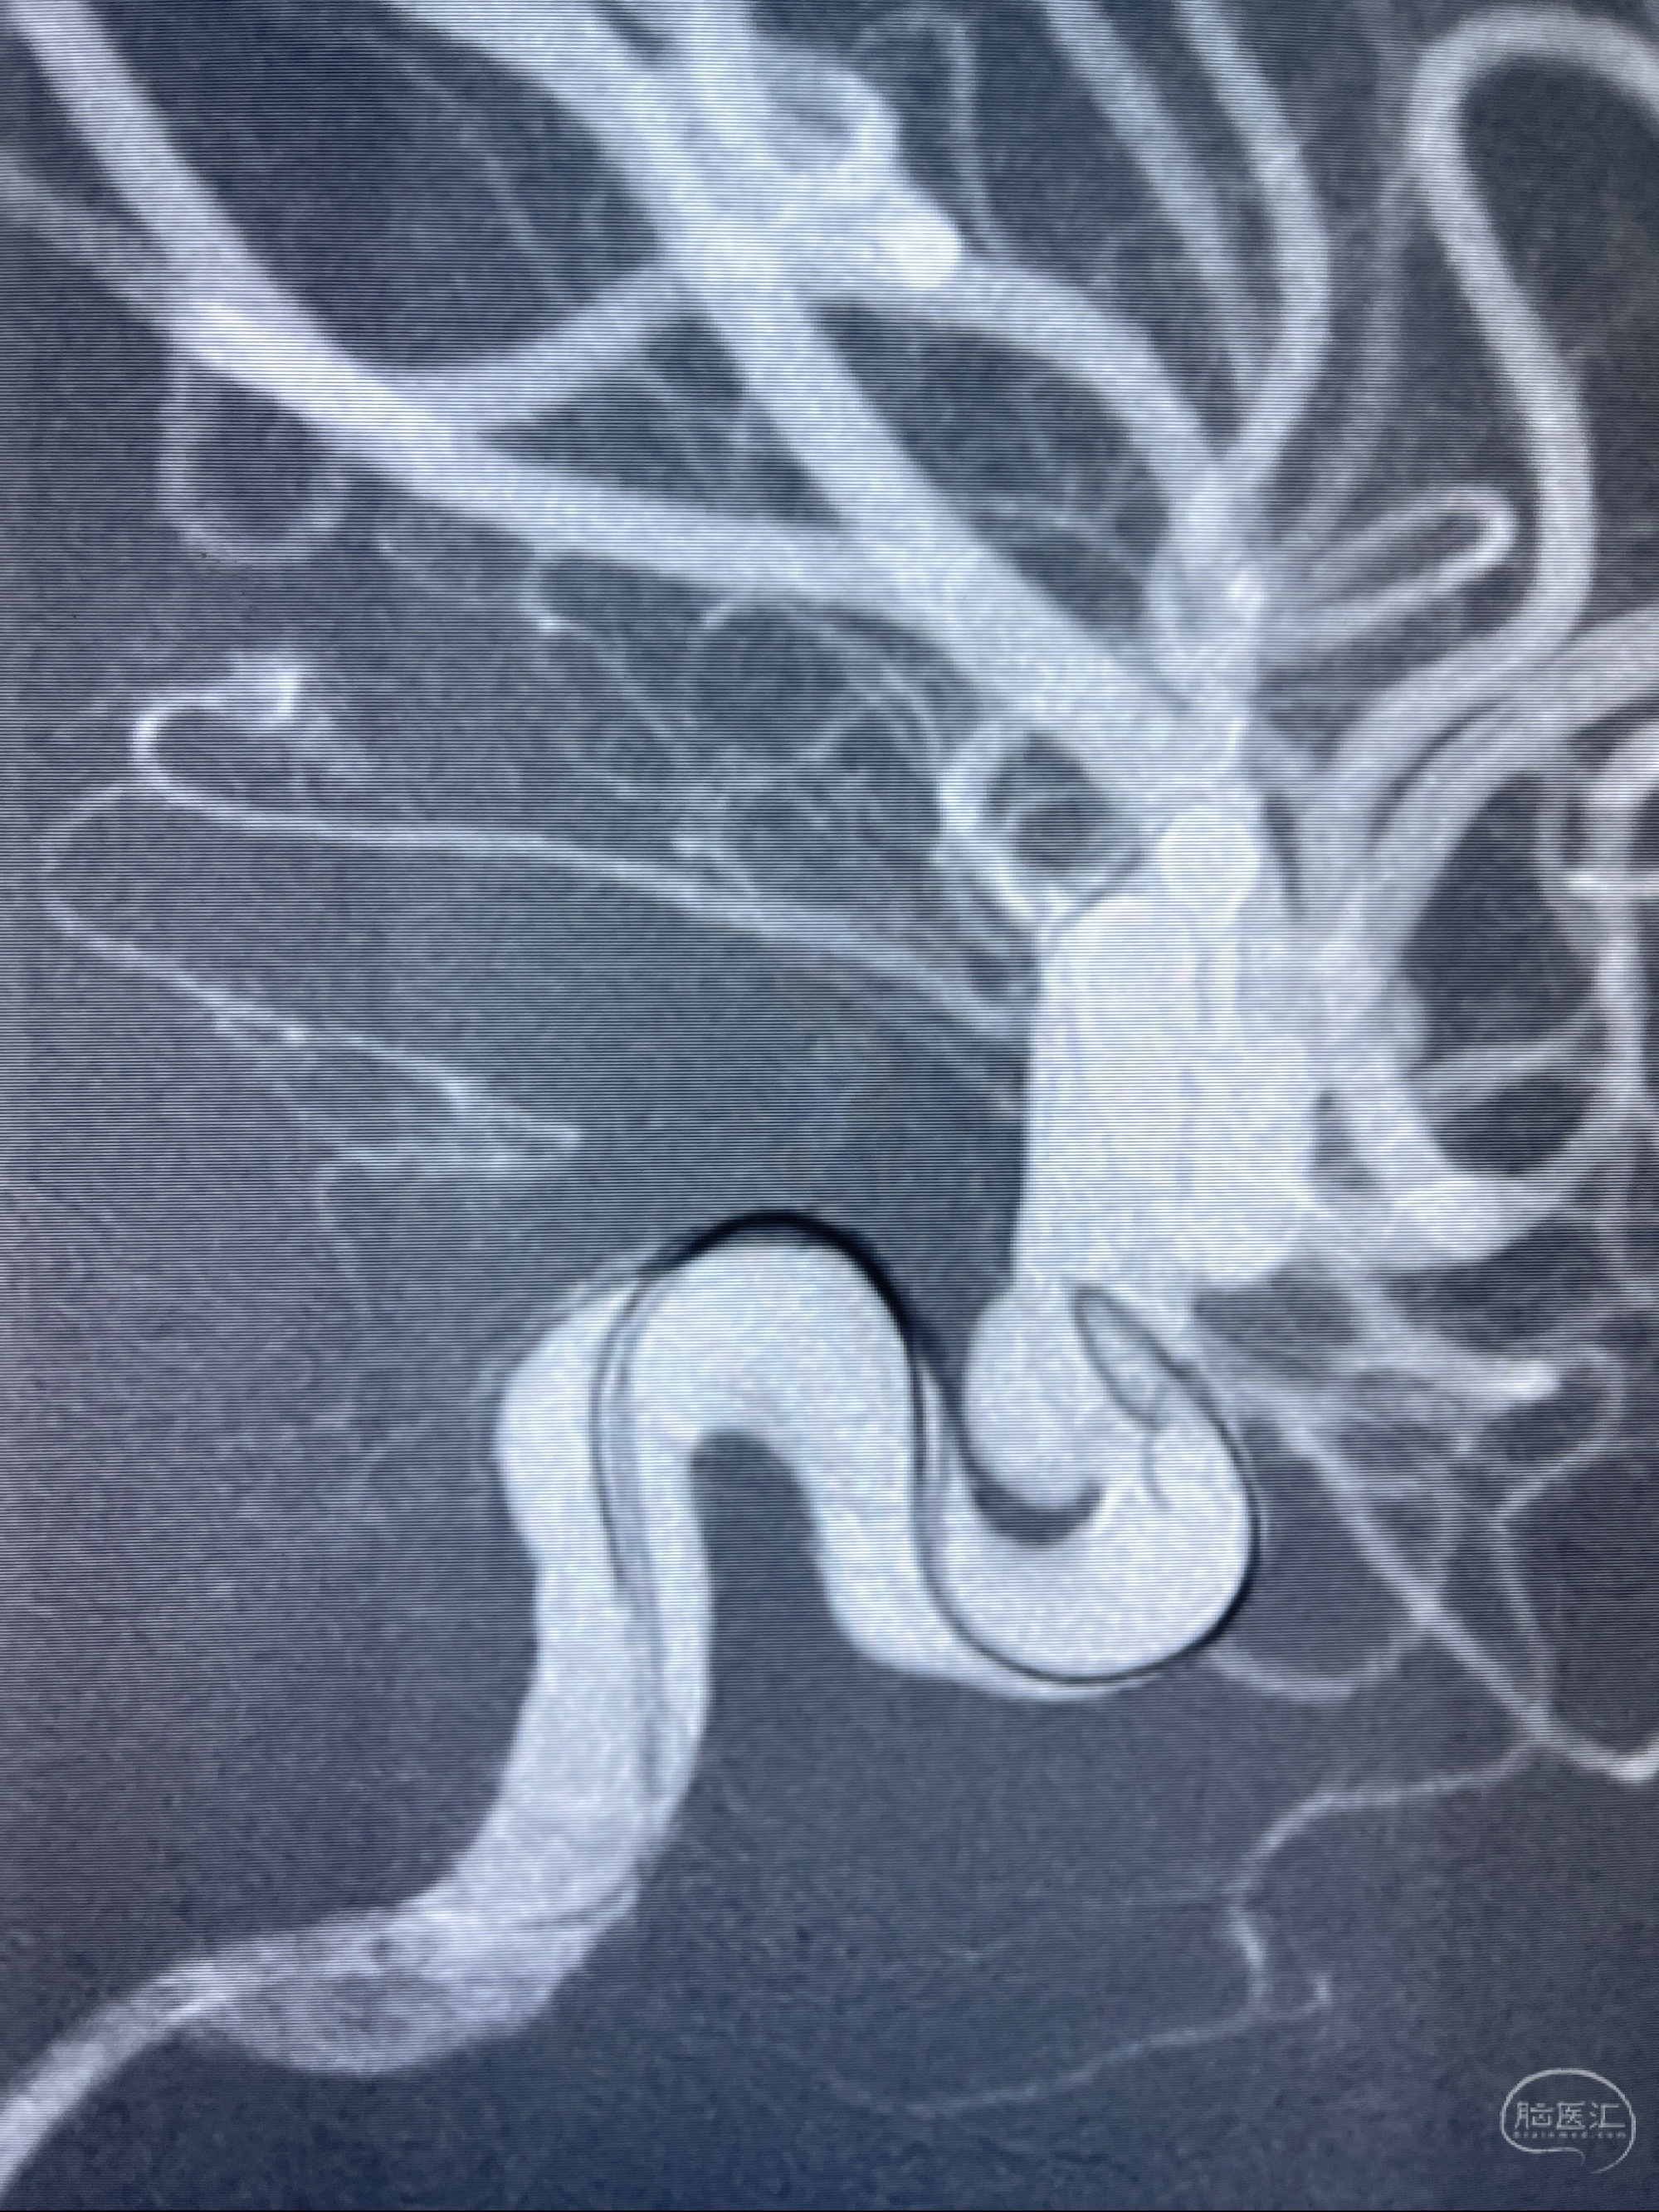

2023-07-27全脑血管造影:双侧颈内动脉眼动脉段动脉瘤,右侧较大

2023-08-01全麻下行双侧颈眼动脉瘤支架辅助栓塞

- pipeling4.5-20mm

- pipeline 4.0-20mm